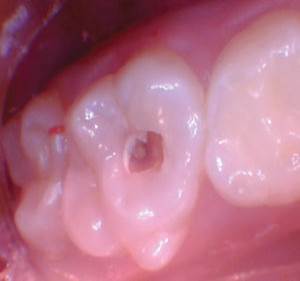

Figura 2. La exposición pulpar se produjo al excavar la dentina infectada (la exposición pulpar no se capturó en la foto). |

Figura 3. Después de quitar el techo de la cámara pulpar. |